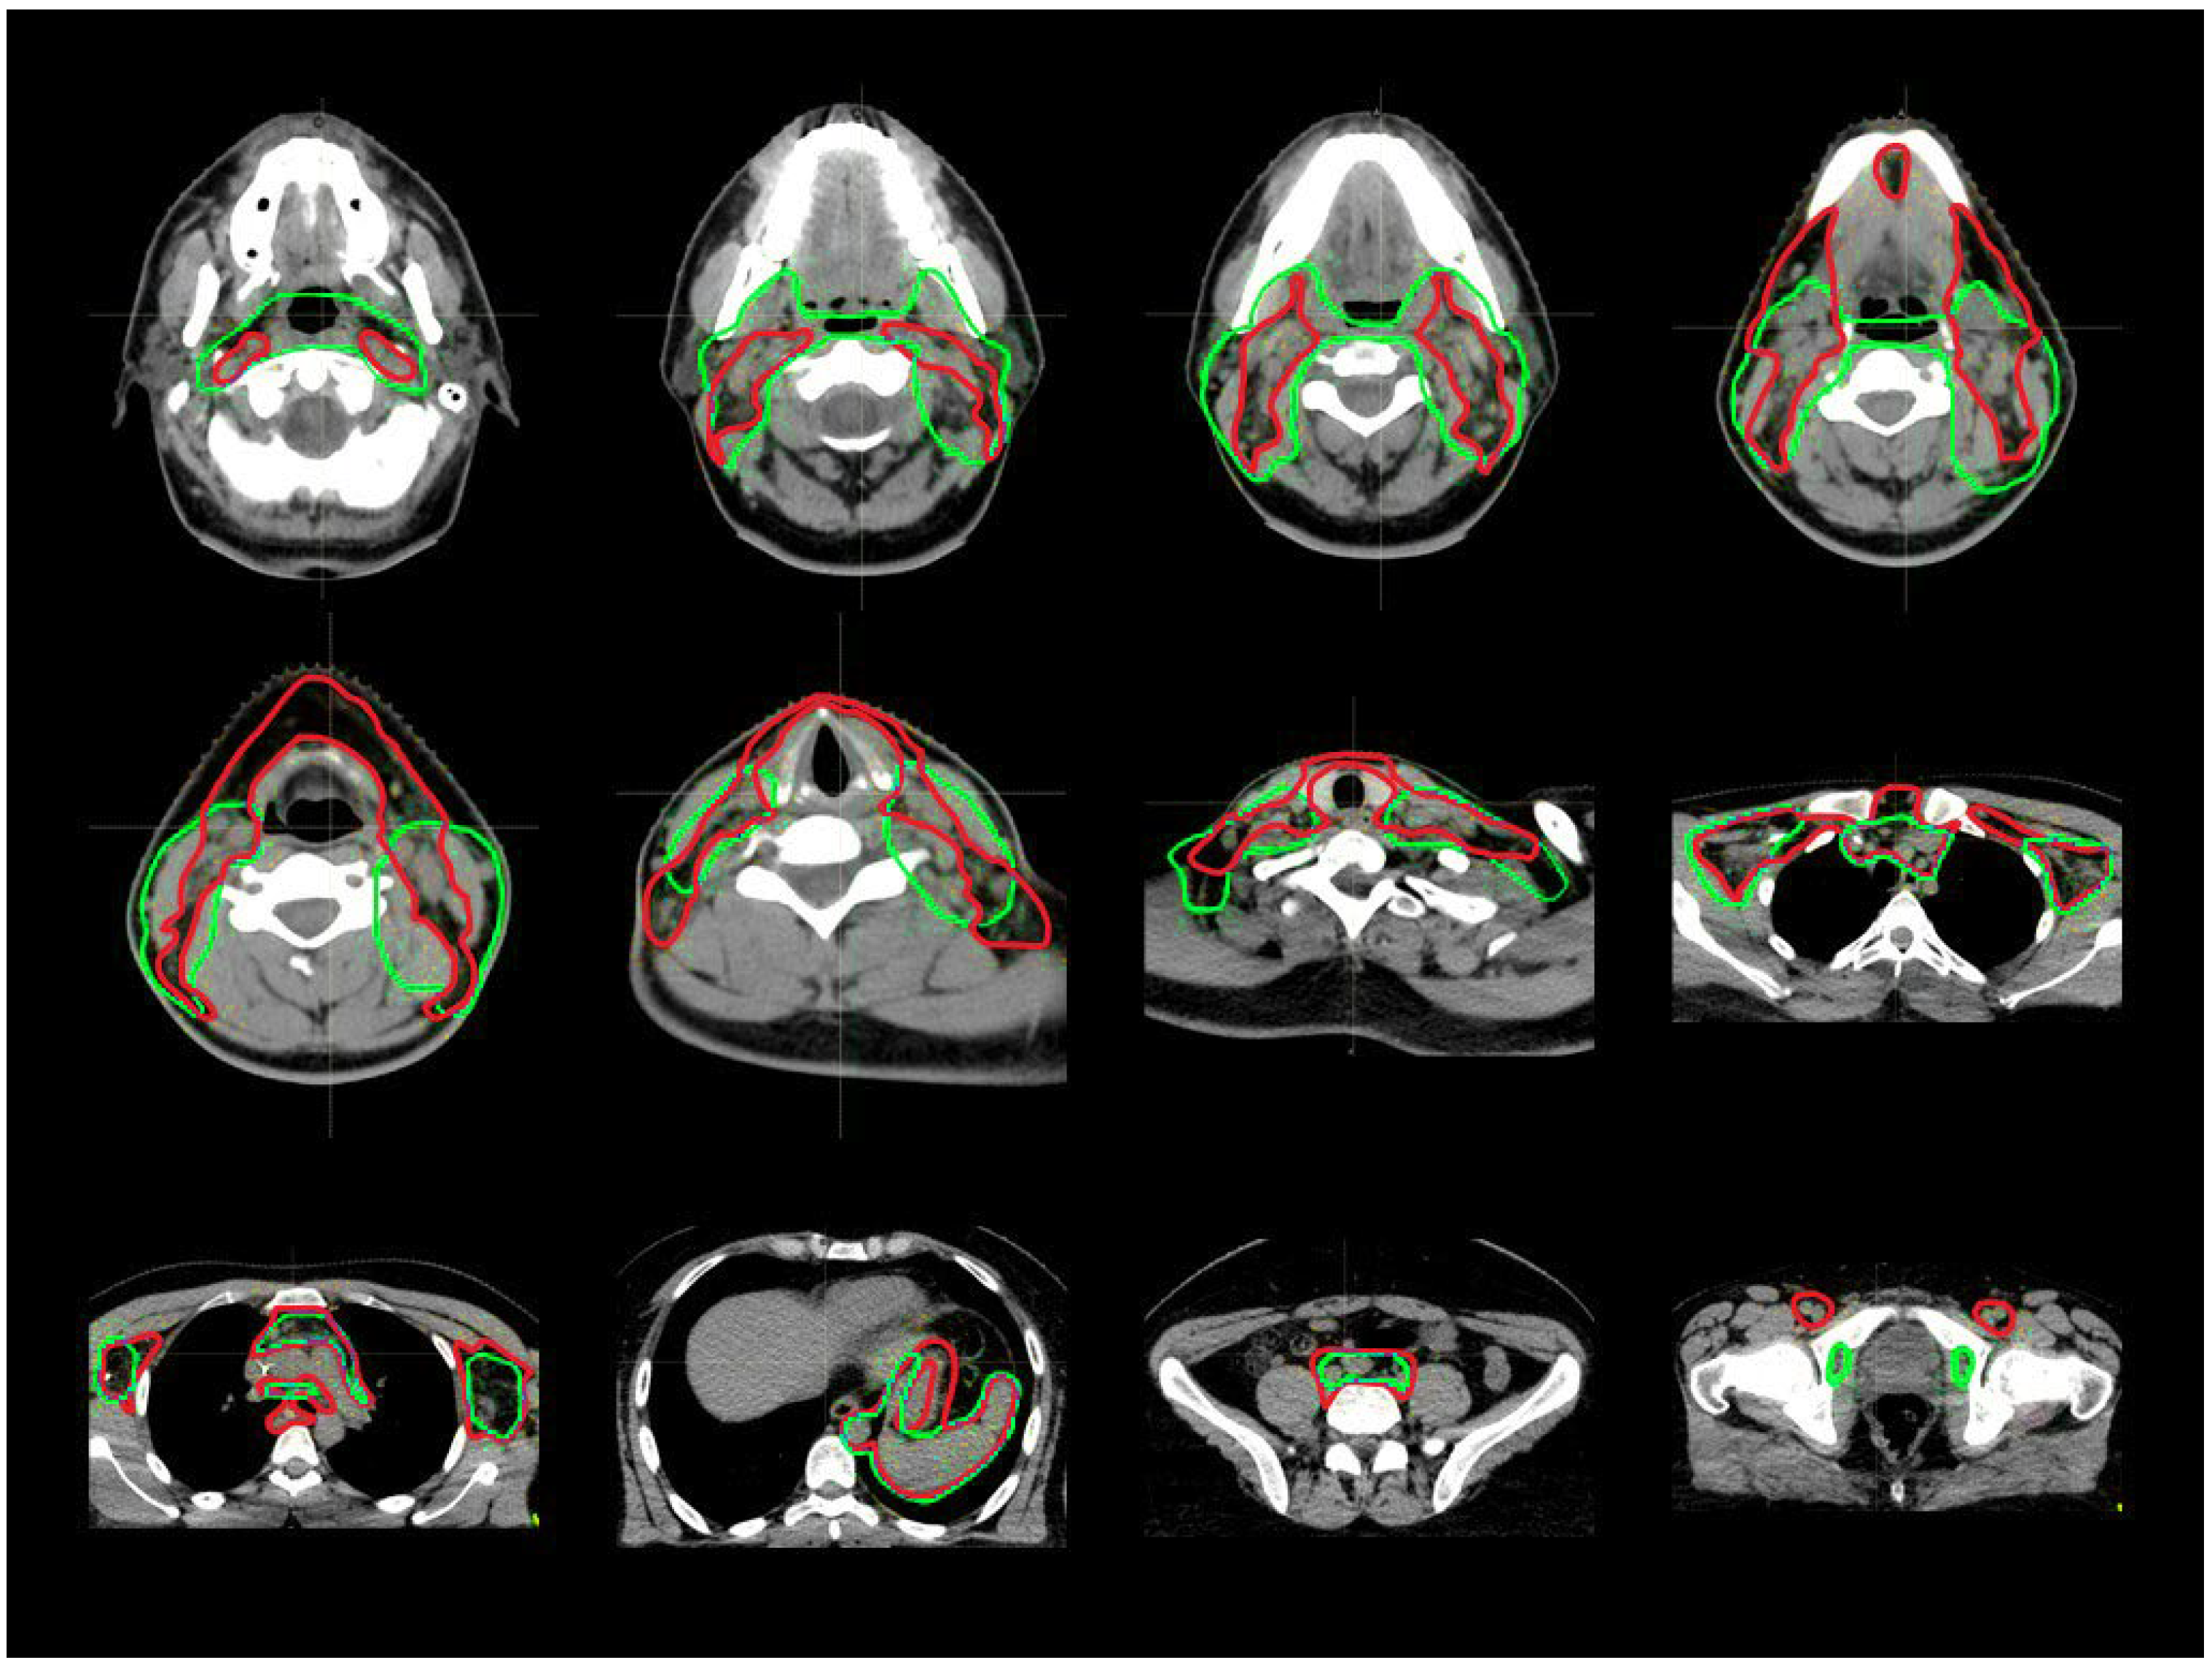

3.1. CTV_LN Inter-/Intraobserver Contouring Variability